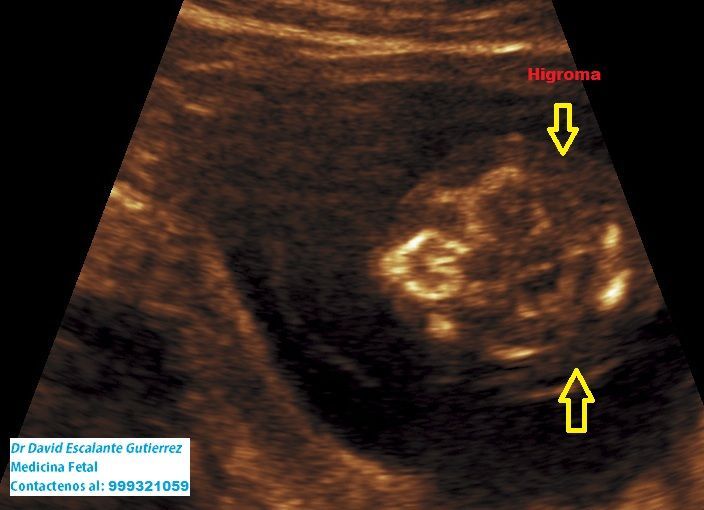

Realizamos las ecografías de viabilidad del embarazo, genética, morfológica, de bienestar fetal, ecocardiografías fetales, así como procedimientos invasivos como biopsia de vellosidades coriales y amniocentesis.

En nuestro Centro de Medicina Fetal disponemos de un equipo altamente calificado de ginecóloga y médico fetal, entrenados y certificados por la Fetal Medicine Foundation, con formación en el Harris Birthright Research Centre del King's College Hospital de Londres, Inglaterra.